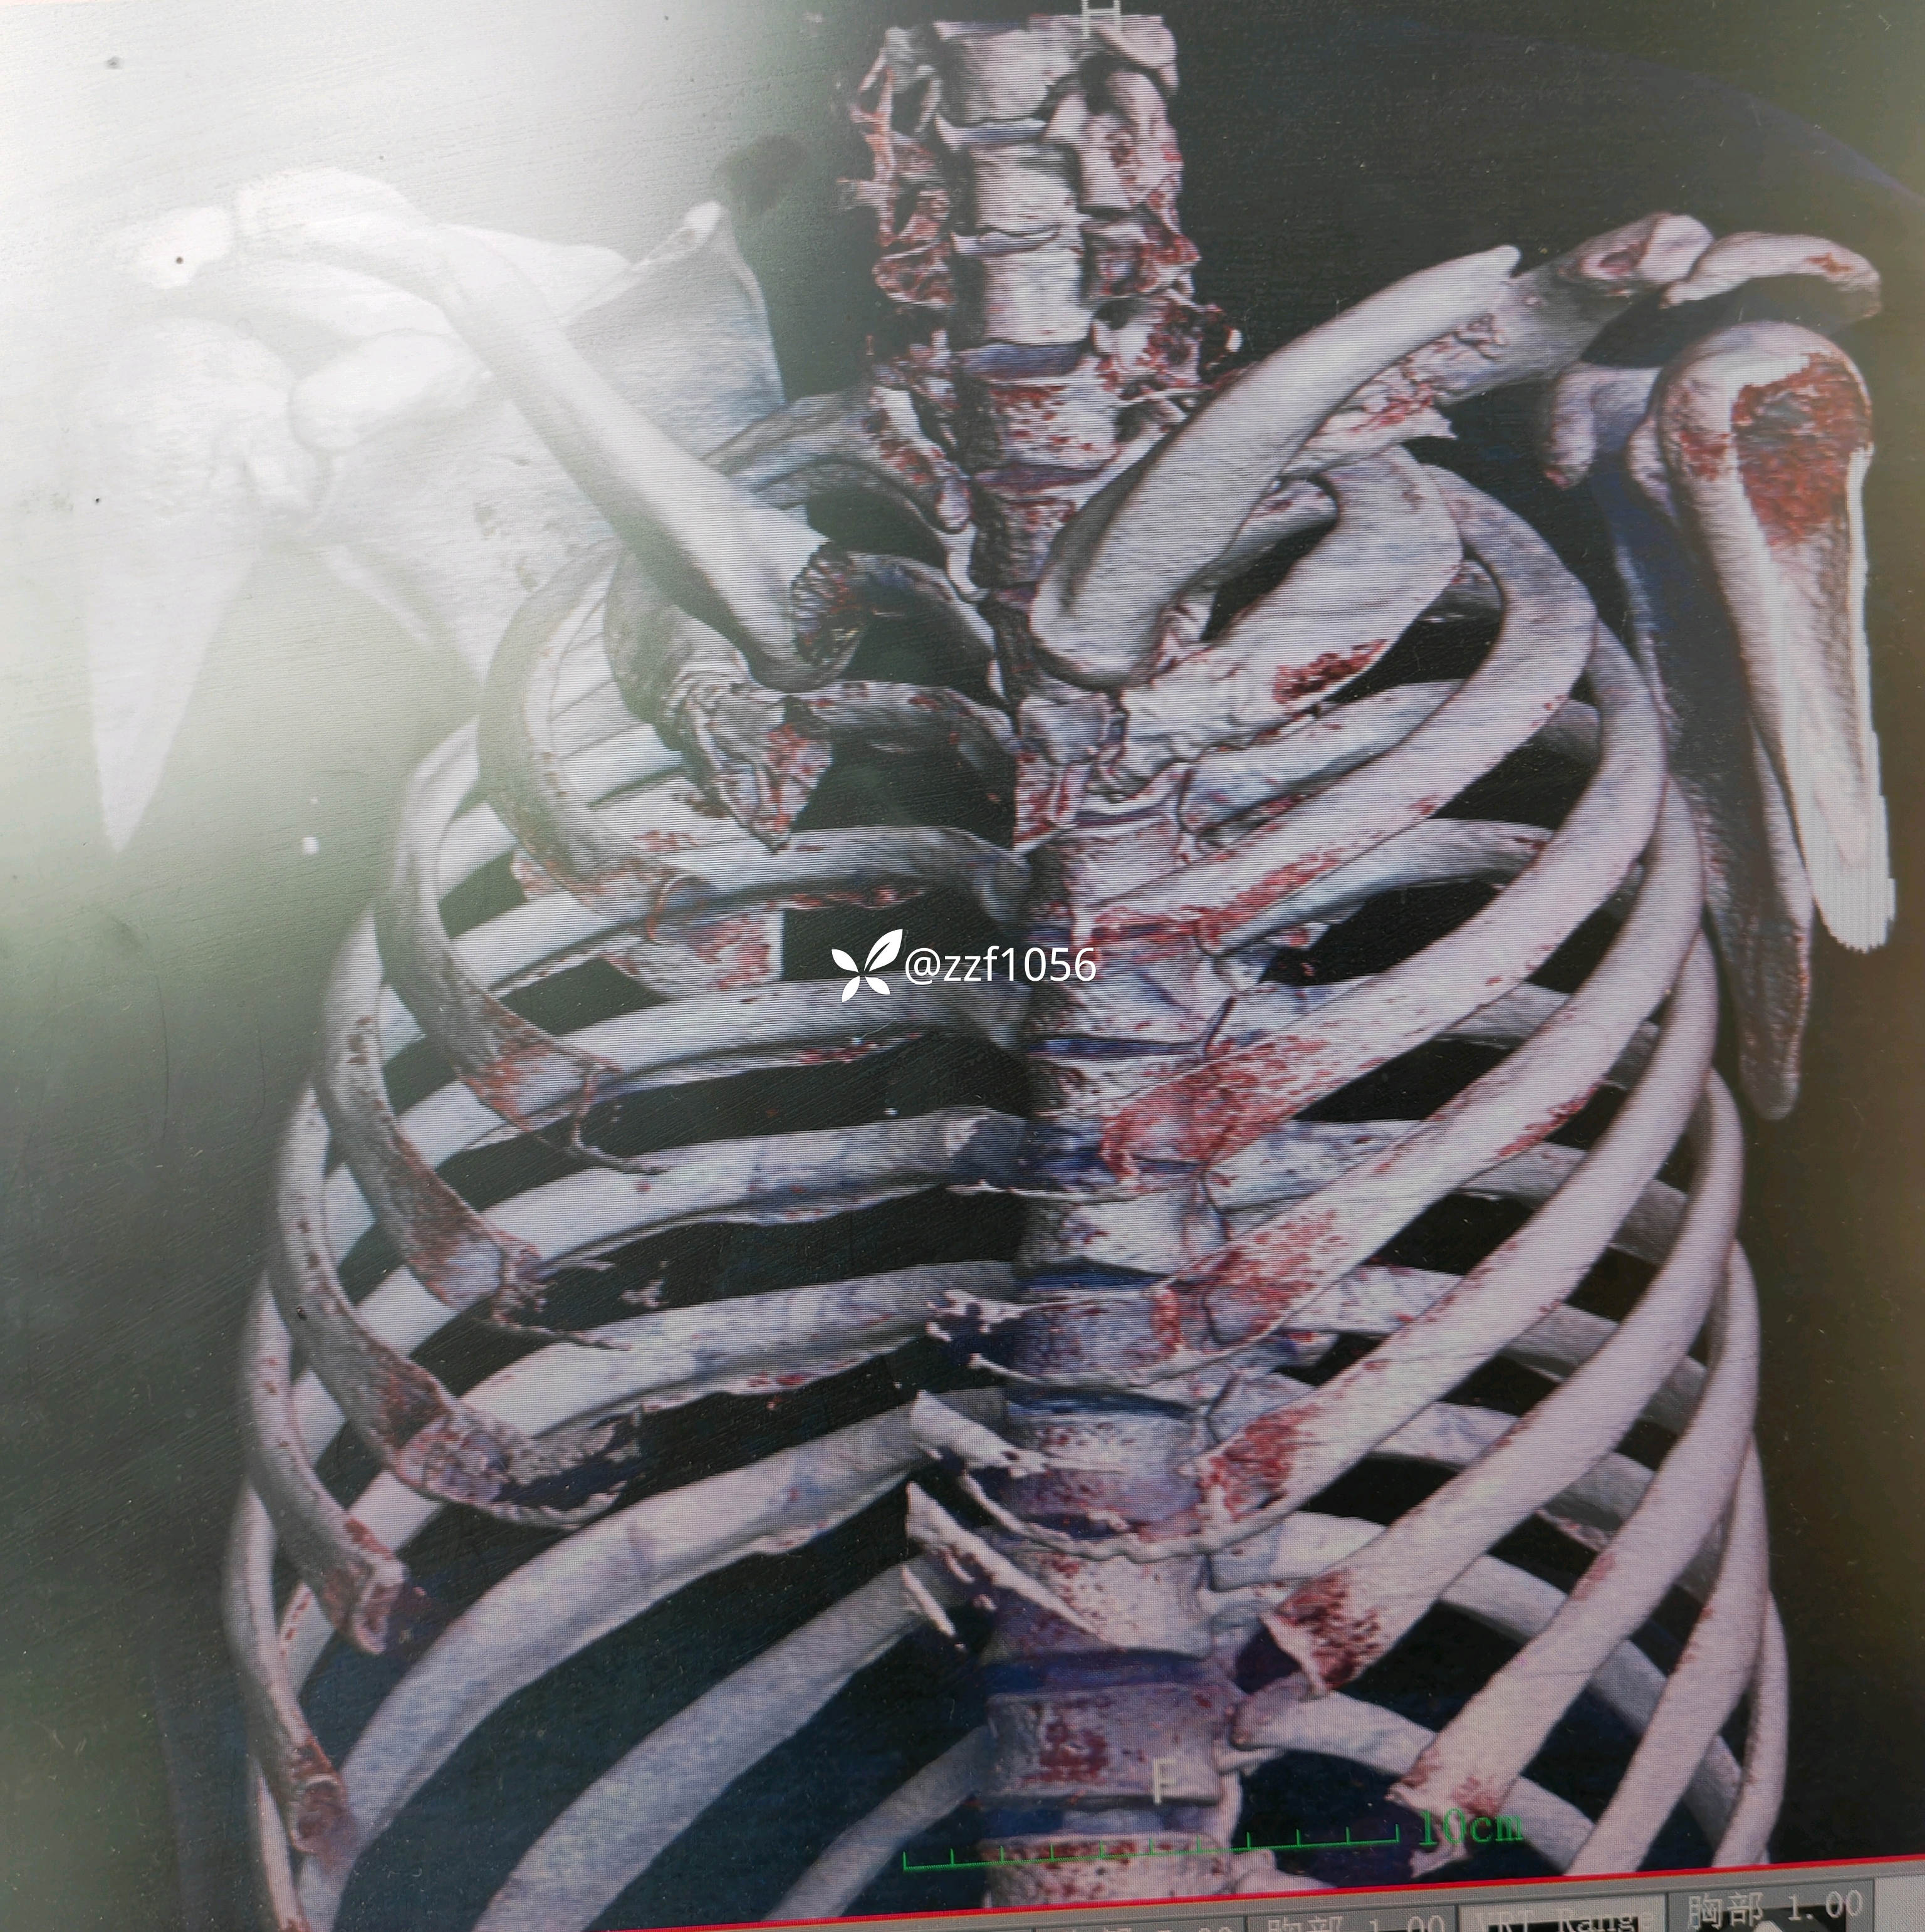

术中作切口后探查未见皮神经,保护好骨膜,清理折端复位临时克氏针固定,后方蝶形骨块较大,nice结改2道钢丝捆扎,复位良好,取最长10孔钢板,貌似钢板有点短,远折端3枚锁定螺钉有效固定,近折端只有2枚螺钉有效固定,第3枚螺钉失效且后方仍有骨块微翘,无奈增加一枚钢丝适宜捆扎。

1.钢丝虽然不收费,与接骨板金属材料不一致,是否能合用?是否会电解反应影响骨折愈合?

2.骨折端跨度较大,接骨板偏短,会出问题吗?器械厂家告知这是最长锁骨钢板,貌似用过12孔,现在单用钢板器械商都不愿意发了。